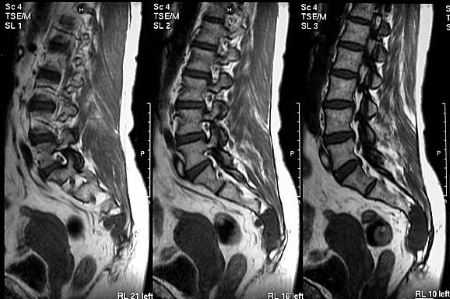

МРТ, УЗИ

С помощью УЗИ можно диагностировать патологии опорно-двигательного аппарата на ранней стадии развития. Исследование проводится для оценки состояния кровеносных сосудов, расположенных около копчика и в органах малого таза. УЗИ — самая безопасная диагностическая процедура, позволяющая с высокой точностью обнаружить опухоли и воспалительные процессы в брюшной полости.

На полученных при МРТ изображениях отчетливо визуализируются мягкие, хрящевые, костные структуры. Диагностическая манипуляция часто используется при неинформативности других процедур.

Рентген

Исследование помогает выявить причины, приведшие к болезненности копчика. С помощью рентгенографии можно диагностировать поясничный остеохондроз, межпозвоночную грыжу, спондилолистез. Процедура позволяет установить также стадию заболевания, степень поражения тканей, количество возникших осложнений.